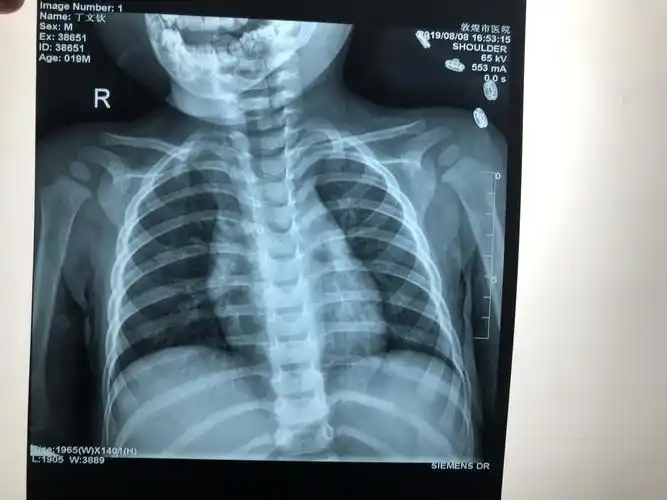

一岁半小儿锁骨骨折治疗一例.